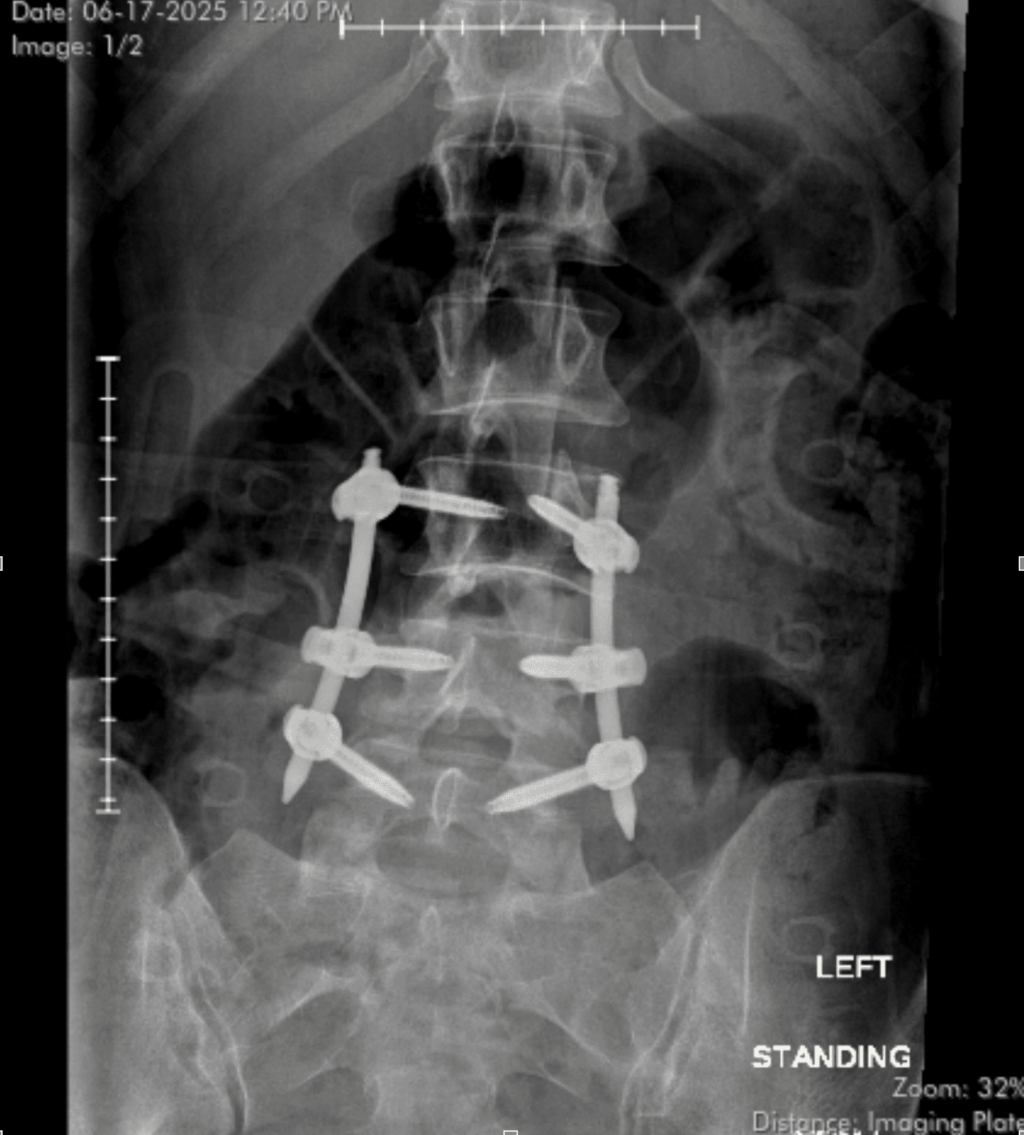

The harm was severe. I used to be transported between two hospitals till I lastly landed at a specialised trauma facility. That’s the place I first heard the analysis: Posterior lumbar spinal fusion with instrumentation from L2 to L5. My vertebrae had collapsed. Titanium rods and screws could be inserted to stabilize my backbone, and the broken discs between them could be repaired.

Surgical procedure was scheduled for the very subsequent morning—June 16. What was purported to be a 1.5–2-hour process stretched to almost 4. My backbone, now fused and bolstered, had turn out to be one thing I didn’t but perceive. I used to be grateful. I used to be terrified. And I used to be alive.

At 1.5 weeks post-op, I nonetheless don’t know if the aches I really feel are from the {hardware}, the incision, or my nerves making an attempt to reconnect. I can’t see my scars but. I’m undecided if what I’m feeling is titanium or trauma. Perhaps each. The ache is worse on the best aspect. Wet days make the whole lot ache—I’ve apparently turn out to be a human barometer.

My surgeon, Dr. Wylie Lopez at OIBOrtho, has been unbelievable. At my 2–3 week follow-up, he advised me I’m progressing sooner than common. I’ve gone from lifting 5 kilos to 10. Three of my 4 bandages are off. One incision continues to be weeping, however not contaminated. I’ve bought another month within the brace—and no, I haven’t set off any steel detectors but.

That is the reality: I don’t know precisely the place this street will take me. However I do know I’m not the identical one that lay damaged in that hospital mattress. I’m stronger now. Not regardless of the titanium in my backbone—however due to it.

Picture Credit: Bridget Mulroy